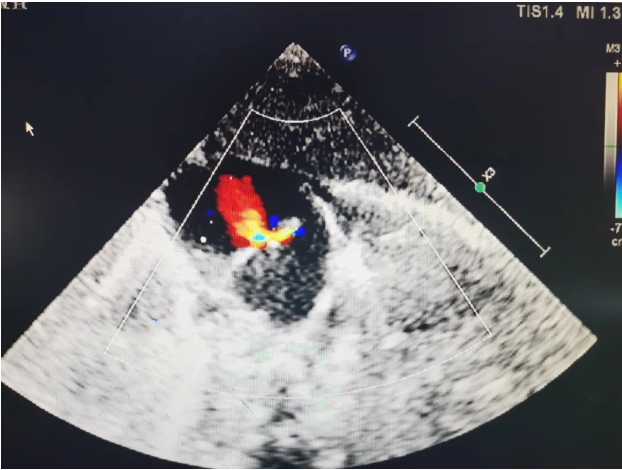

胸骨旁大动脉短轴切面:主-肺动脉间隔缺损、右肺动脉异常起源于升主动脉。

CDFI:肺动脉主干内血流充盈,双向分流,左、右肺动脉的血流由主动脉和肺动脉共同供给。